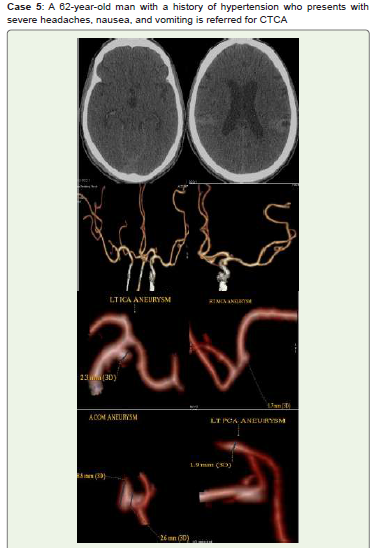

Figure 5:Acute SAH is seen on noncontrast CT (A, B). Multiple saccular

aneurysms of intracranial left clinoid ICA (C5), ACOM, right MCA, and

fusiform aneurysm of left posterior cerebral artery (PCA) are seen on CTCA

3D-VR images (C-H). Managed conservatively & on regular follow up.